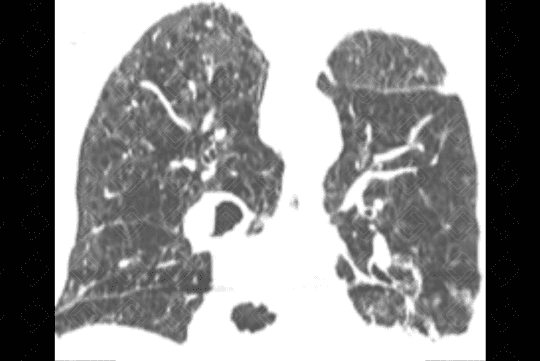

Descrição das figuras 1 e 2: Radiografia de tórax PA e perfil evidenciando os sinais clássicos de doença pulmonar obstrutiva crônica: diafragma retificado, coração alongado e verticalizado, além de aumento anteroposterior da caixa torácica.

• Radiografia de tórax: O r endimento da avaliação da DPOC pelo estudo radiológico simples é bastante limitado, não havendo anormalidade na radiografia se não existir aprisionamento de ar. Quando há aprisionamento de ar, os critérios mais seguros são: diafragma rebaixado ou retificado; aumento do espaço retroesternal (maior que 3 cm) e persistência do aumento do espaço retroesternal na expiração, coração alongado e verticalizado, presença de bolhas é inferida pela identificação de área de maior radiotransparência, avascular, podendo ou não estar delimitada por fina linha branca (figuras 1 e 2) ;